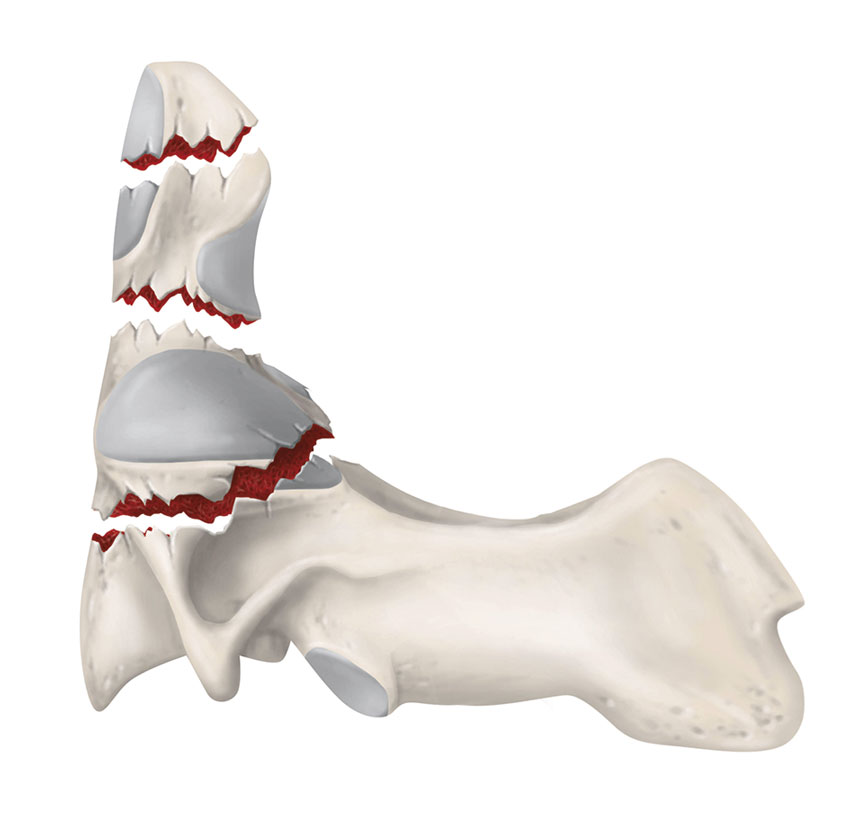

Frakturer i dens axis (C2)

Dens axis-frakturer utgör 18 procent av alla halsryggsfrakturer, och hos patienter över 80 år står de för 50 procent [13].

Densfrakturer klassificeras utifrån frakturlokalisation. Typ 1 utgör skada i toppen av dens och är ovanlig. Typ 2-frakturer är vanligast och är lokaliserade i övergången mellan dens och kotkroppen. Typ 3-skador förlöper ner i C2:s kotkropp [14].

Patienter med densfrakturer uppvisar sällan neurologisk påverkan vid ankomst till sjukhus. Har våldet varit så kraftigt att det medfört en större dislokation påverkas medulla i så hög grad att patienten oftast avlider.

Typ 1- och typ 3-skador är oftast stabila och kan behandlas med halskrage. För typ 2-skadorna saknas internationell konsensus om optimal behandling; alternativen är hård halskrage, haloväst eller kirurgisk fixation [13]. Risken för pseudartrosutveckling vid konservativ behandling är relativt stor, framför allt vid typ 2, men viss risk finns även vid typ 3-skador [10]. Vid större felställning bör frakturen reponeras, ofta krävs även kirurgisk fixation.

Lokalisation av densfrakturer. Typ 1: genom toppen av dens. Typ 2: genom basen av dens. Typ 3: genom dens och ner i C2.